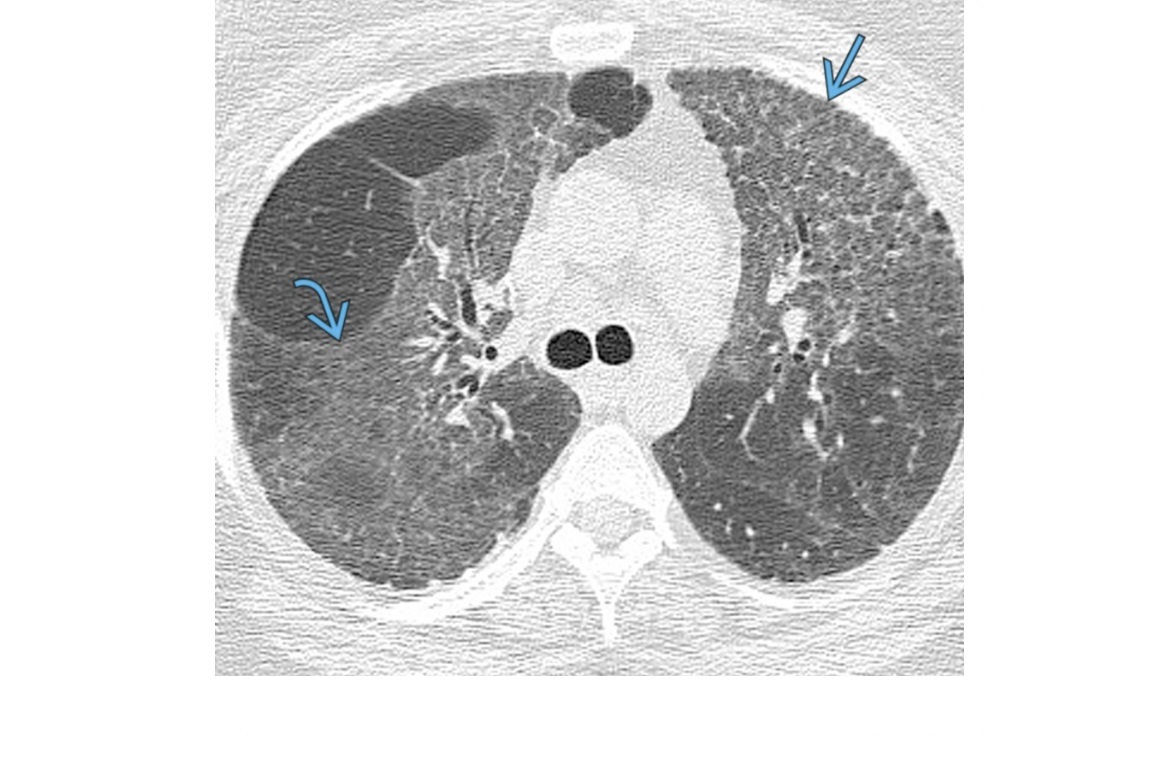

Mucormycosis

Difficult to discern radiologically and clinically from aspergillosis

Can have halo sign but more specific reverse halo sign

unlike COP, peripheral capsule in the reversed halo sign tends to be thicker